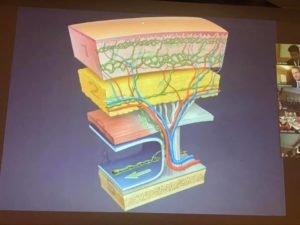

Первый курс ICPF был организован в г. Гент, Бельгия 20 лет назад, на заре применения перфорантных лоскутов в реконструктивной хирургии. Сейчас перфорантрные лоскуты можно назвать наиболее распространенной техников в этой ветви хирургии, а само мероприятие переросло в крупный международный форум.

Уникальная черта этого курса – обмен опытом в хирургии с использованием перфорантных лоскутов – хирургическими приёмами и тонкостями, техниками и т.п. в дружеской атмосфере. Программа курса насыщена лекциями по различным видам перфорантных лоскутов, особенностям планирования операций и подготовки лоскутов, операциями и кадавер-демонстрациями. Среди изюминок курса – выполнение гуру реконструктивной хирургии, профессором Исао Кошима (Isao Koshima), лимфо-венозных анастомозов у пациентки с лимфедемой.